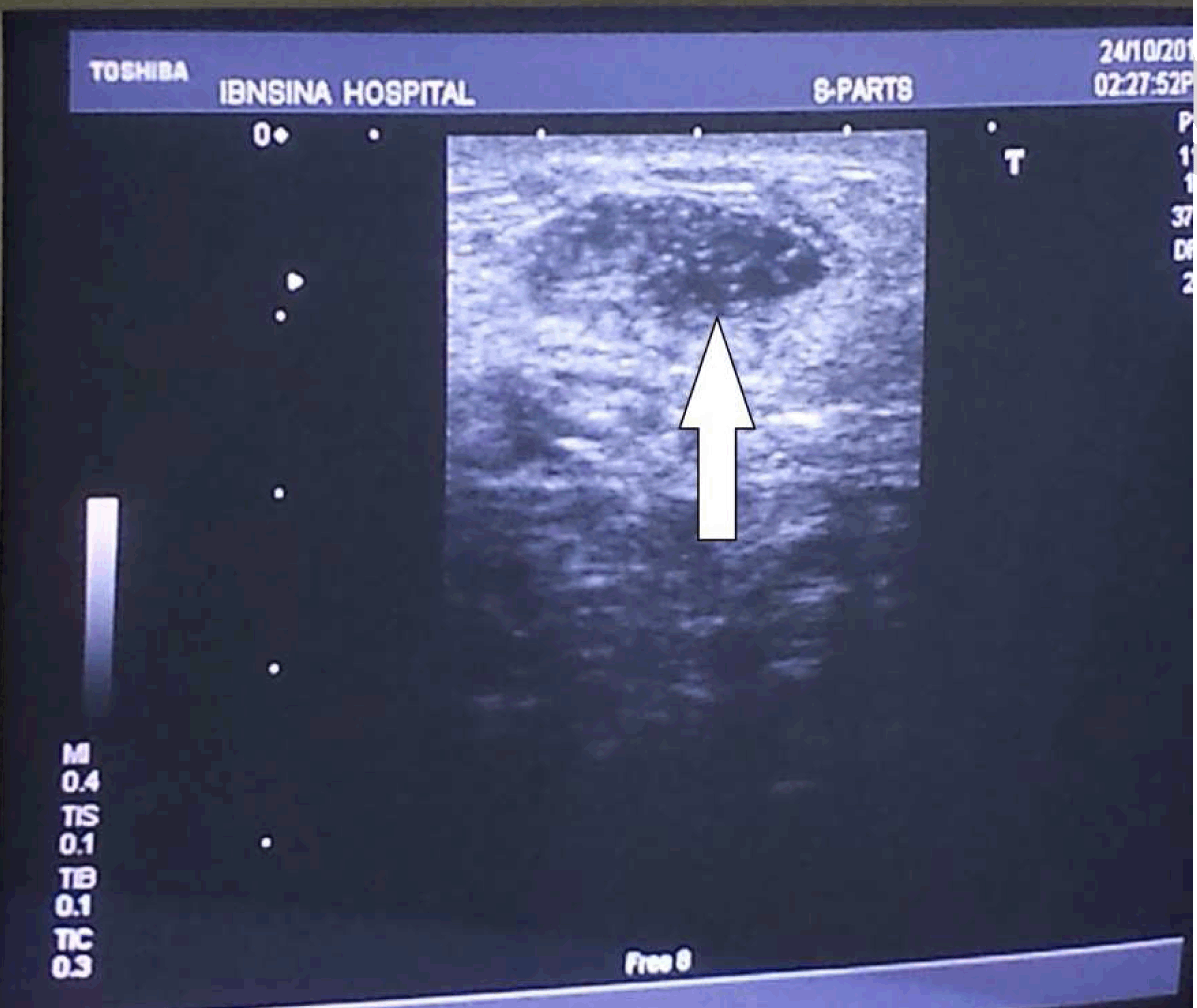

On greyscale ultrasonography the swelling represented a hypoechoic region (Figure 3). A Doppler ultrasound was performed, thus confirming the patency of the fistula.

Figure 3: Greyscale ultrasound denoting the hypoechoic area of the swelling (arrow).